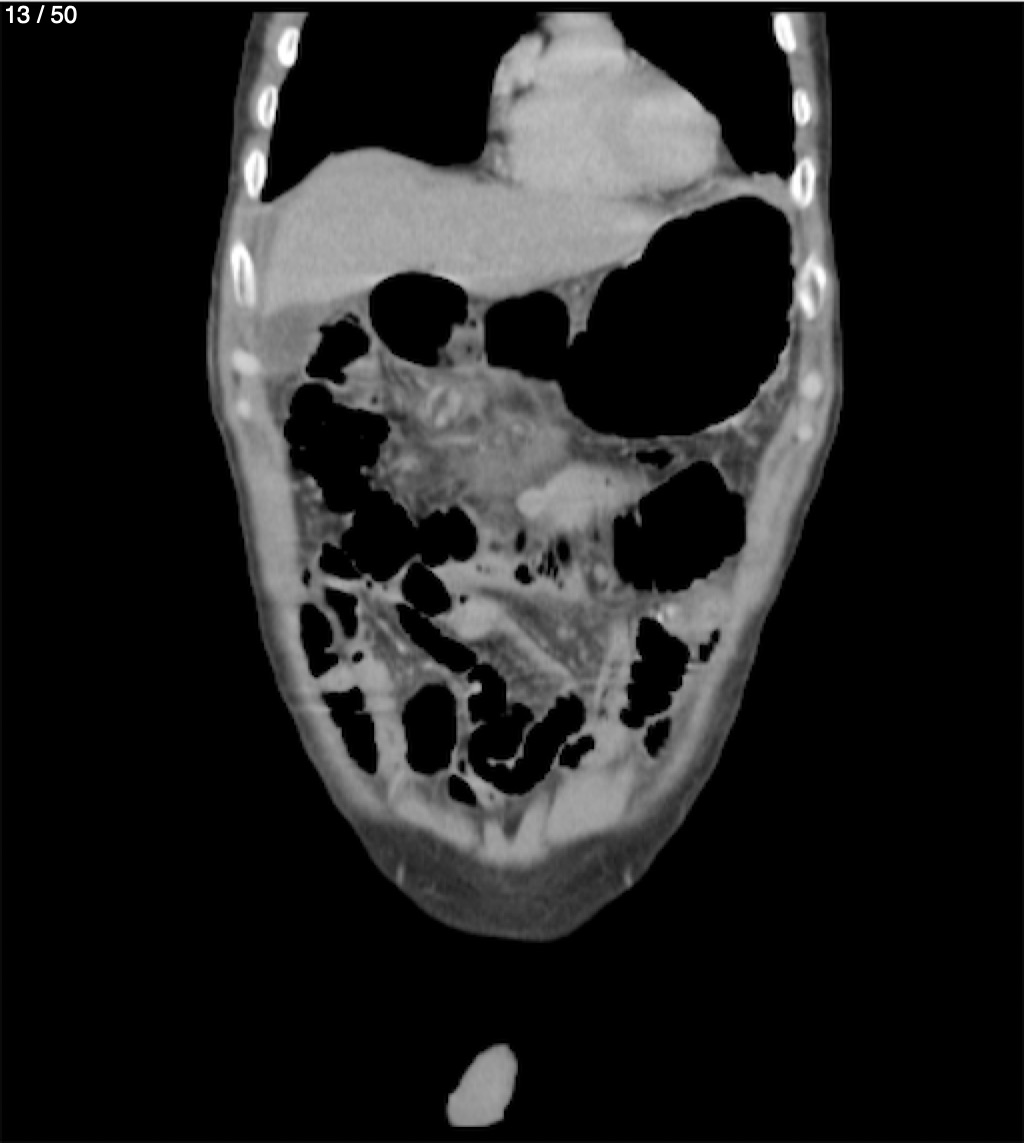

Alonso Victorio Ruiz 62A - T.C Abdomen Syc